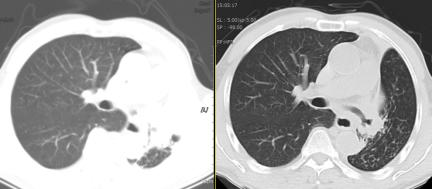

病灶切除前后CT对比:左主支气管被肿瘤完全阻塞、左肺不张(左),右图示肿瘤切除后左主支气管完全通畅、左肺复张(右)